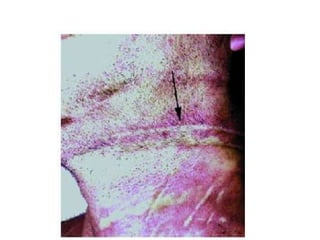

Postmortempicture of strangulation:(1) General(2) SpecialfeaturesAll are neck signs:       - Ligature marks:        . Low in the neck below the thyroid cartilage.        . Transverse.        . Complete.        . Deep all through.        . Abrasions and contusions taking the shape of the ligatingmaterial.       - Inward fracture of the hyoidbone and the thyroid cartilage maybefractured.       - Contusions and lacerations of the neck muscles.**Homicidal, suicidal or accidental

Postmortempicture of strangulation:(1)General(2) SpecialfeaturesAll are neck signs: - Ligature marks: . Low in the neck below the thyroid cartilage. . Transverse. . Complete. . Deep all through. . Abrasions and contusions taking the shape of the ligatingmaterial. - Inward fracture of the hyoidbone and the thyroid cartilage maybefractured. - Contusions and lacerations of the neck muscles.**Homicidal, suicidal or accidental